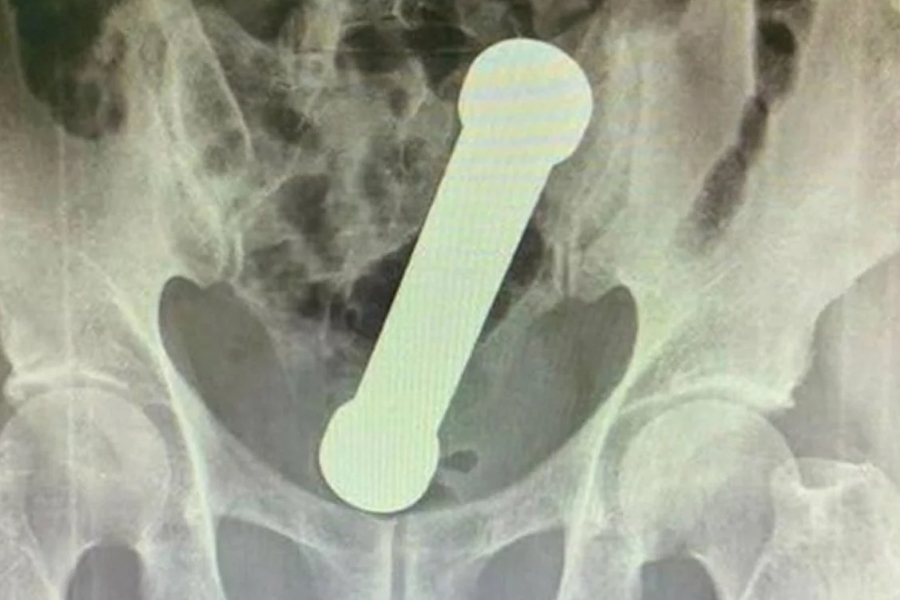

Haltere de 2kg dentro do homem | Foto: Reprodução / Artigo Surgery Case Reports

Segundo a equipe médica, o homem deu entrada no hospital com dores abdominais e com dificuldade de evacuar. Foi realizado radiografias e os médicos constataram que havia um objeto estranho. Ao examinar as imagens foi identificado um haltere de dois quilos dentro do paciente.

O homem foi levado ao centro cirúrgico, onde os médicos retiram o objeto de cerca de 20 centímetros sem a ajuda de pinça ou instrumentos.